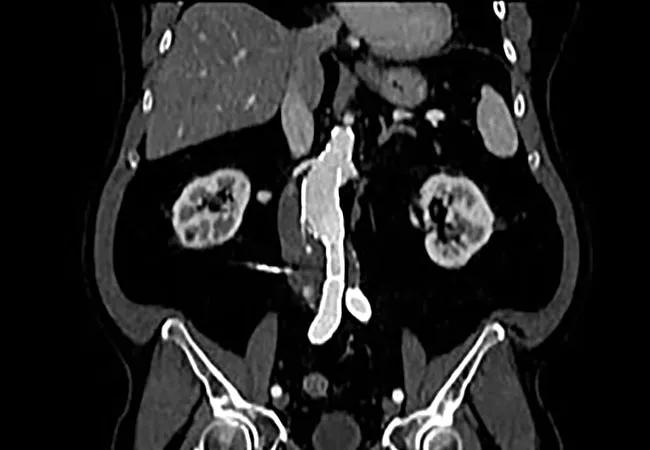

A team of Cleveland Clinic vascular surgeons has found that their practice is bucking the national trend toward decreased use of open aortic repair (OAR) for abdominal aortic aneurysms (AAAs), prompting a call for a national discussion around future directions for vascular surgery training.